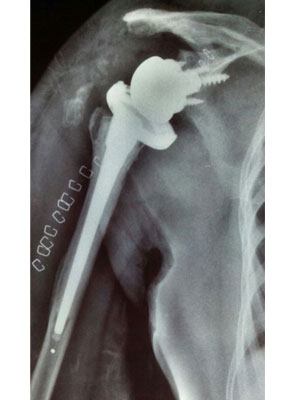

Pre Shoulder Replacement Surgery

X-Ray for Rotator Cuff Arthropathy

Post Shoulder Replacement